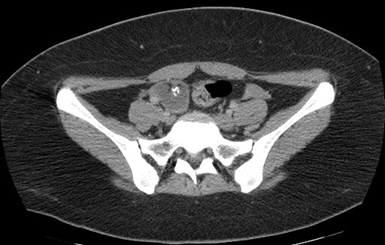

Four days later, magnetic resonance imaging (MRI) of the skull was performed, reporting brain parenchyma of both hemispheres, basal ganglia, thalamus, stem structure, and cerebellum of normal morphology and intensity (Figures 1 and 2). Likewise, an electroencephalogram (EEG) is performed during wakefulness and sleep, reporting within normal limits and observing epileptiform activity.

Figure 1 Brain MRI in axial section without evidence of intraparenchymal or structural lesions.